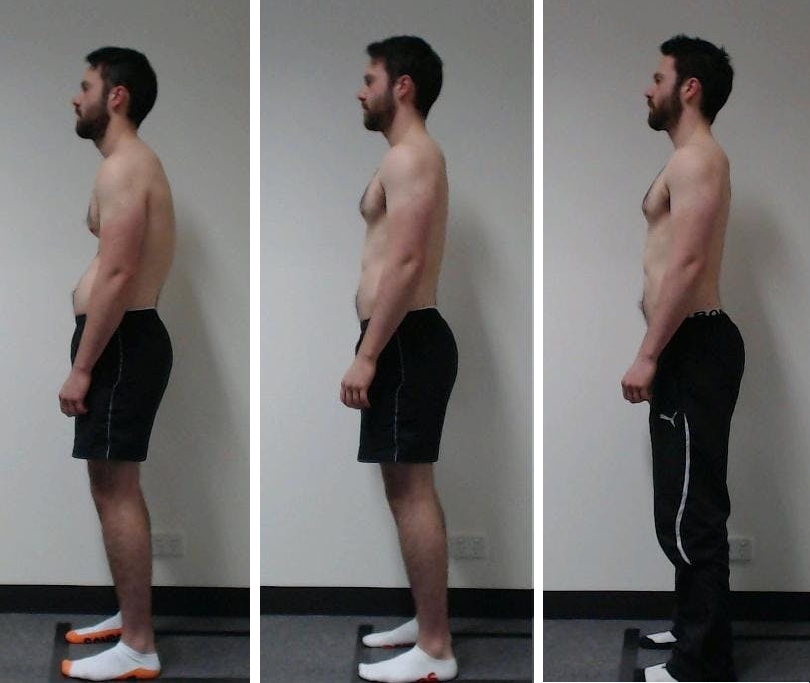

Guardate queste fotografie. Ecco cosa è successo a coloro che non hanno fatto attenzione ai sintomi. Oggi queste persone sono completamente senza speranza, e molti di loro non hanno nessuno su cui contare per le cure. Volete davvero un destino simile?

— Ognuna di queste persone pensava che non sarebbe mai successo a lei! Ma ecco il risultato: perdita totale di mobilità, paralisi, amputazione — dipendenza a vita dall’aiuto altrui e LA SEDIA A ROTELLE! Più del 90% diventa disabile solo perché non ha preso le giuste misure in tempo. L’USURA DELLE ARTICOLAZIONI INIZIA IN SILENZIO — ignorare il dolore significa buttare la propria vita nel secchio!